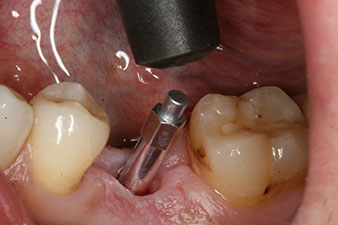

After healing of the soft tissue, the implant stability was measured again before delivery of the prosthetic restoration.

Both values were virtually unchanged and were between the medium and the high range – where the lower value is always used as the reference value that determines the treatment.

Therefore, successful osseointegration and adequate biological stability could be recorded, which enabled an impression to be taken in the same session.